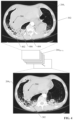

• FIG. 3 a is an example 2D image 204 prior to segmentation

• FIG. 3 b is the example 2D image 204 after 3D segmentation.

• a medical imaging system can analyze the content of the resulting 2D images 204 to identify gradients, borders, or contours within the images 204 and delineate these contours using a suitable labeling convention; e.g., by marking the identified contours with segmentation lines 302 (depicted as heavy white lines in FIG. 3 b , although segmentation lines 302 may be rendered in any suitable color).

• This 3D segmentation process can identify and mark the contours of an organ, a tumor, a cavity, or another area of interest.

• the right lung 304 and left lung 306 have been delineated using segmentation lines 302 .